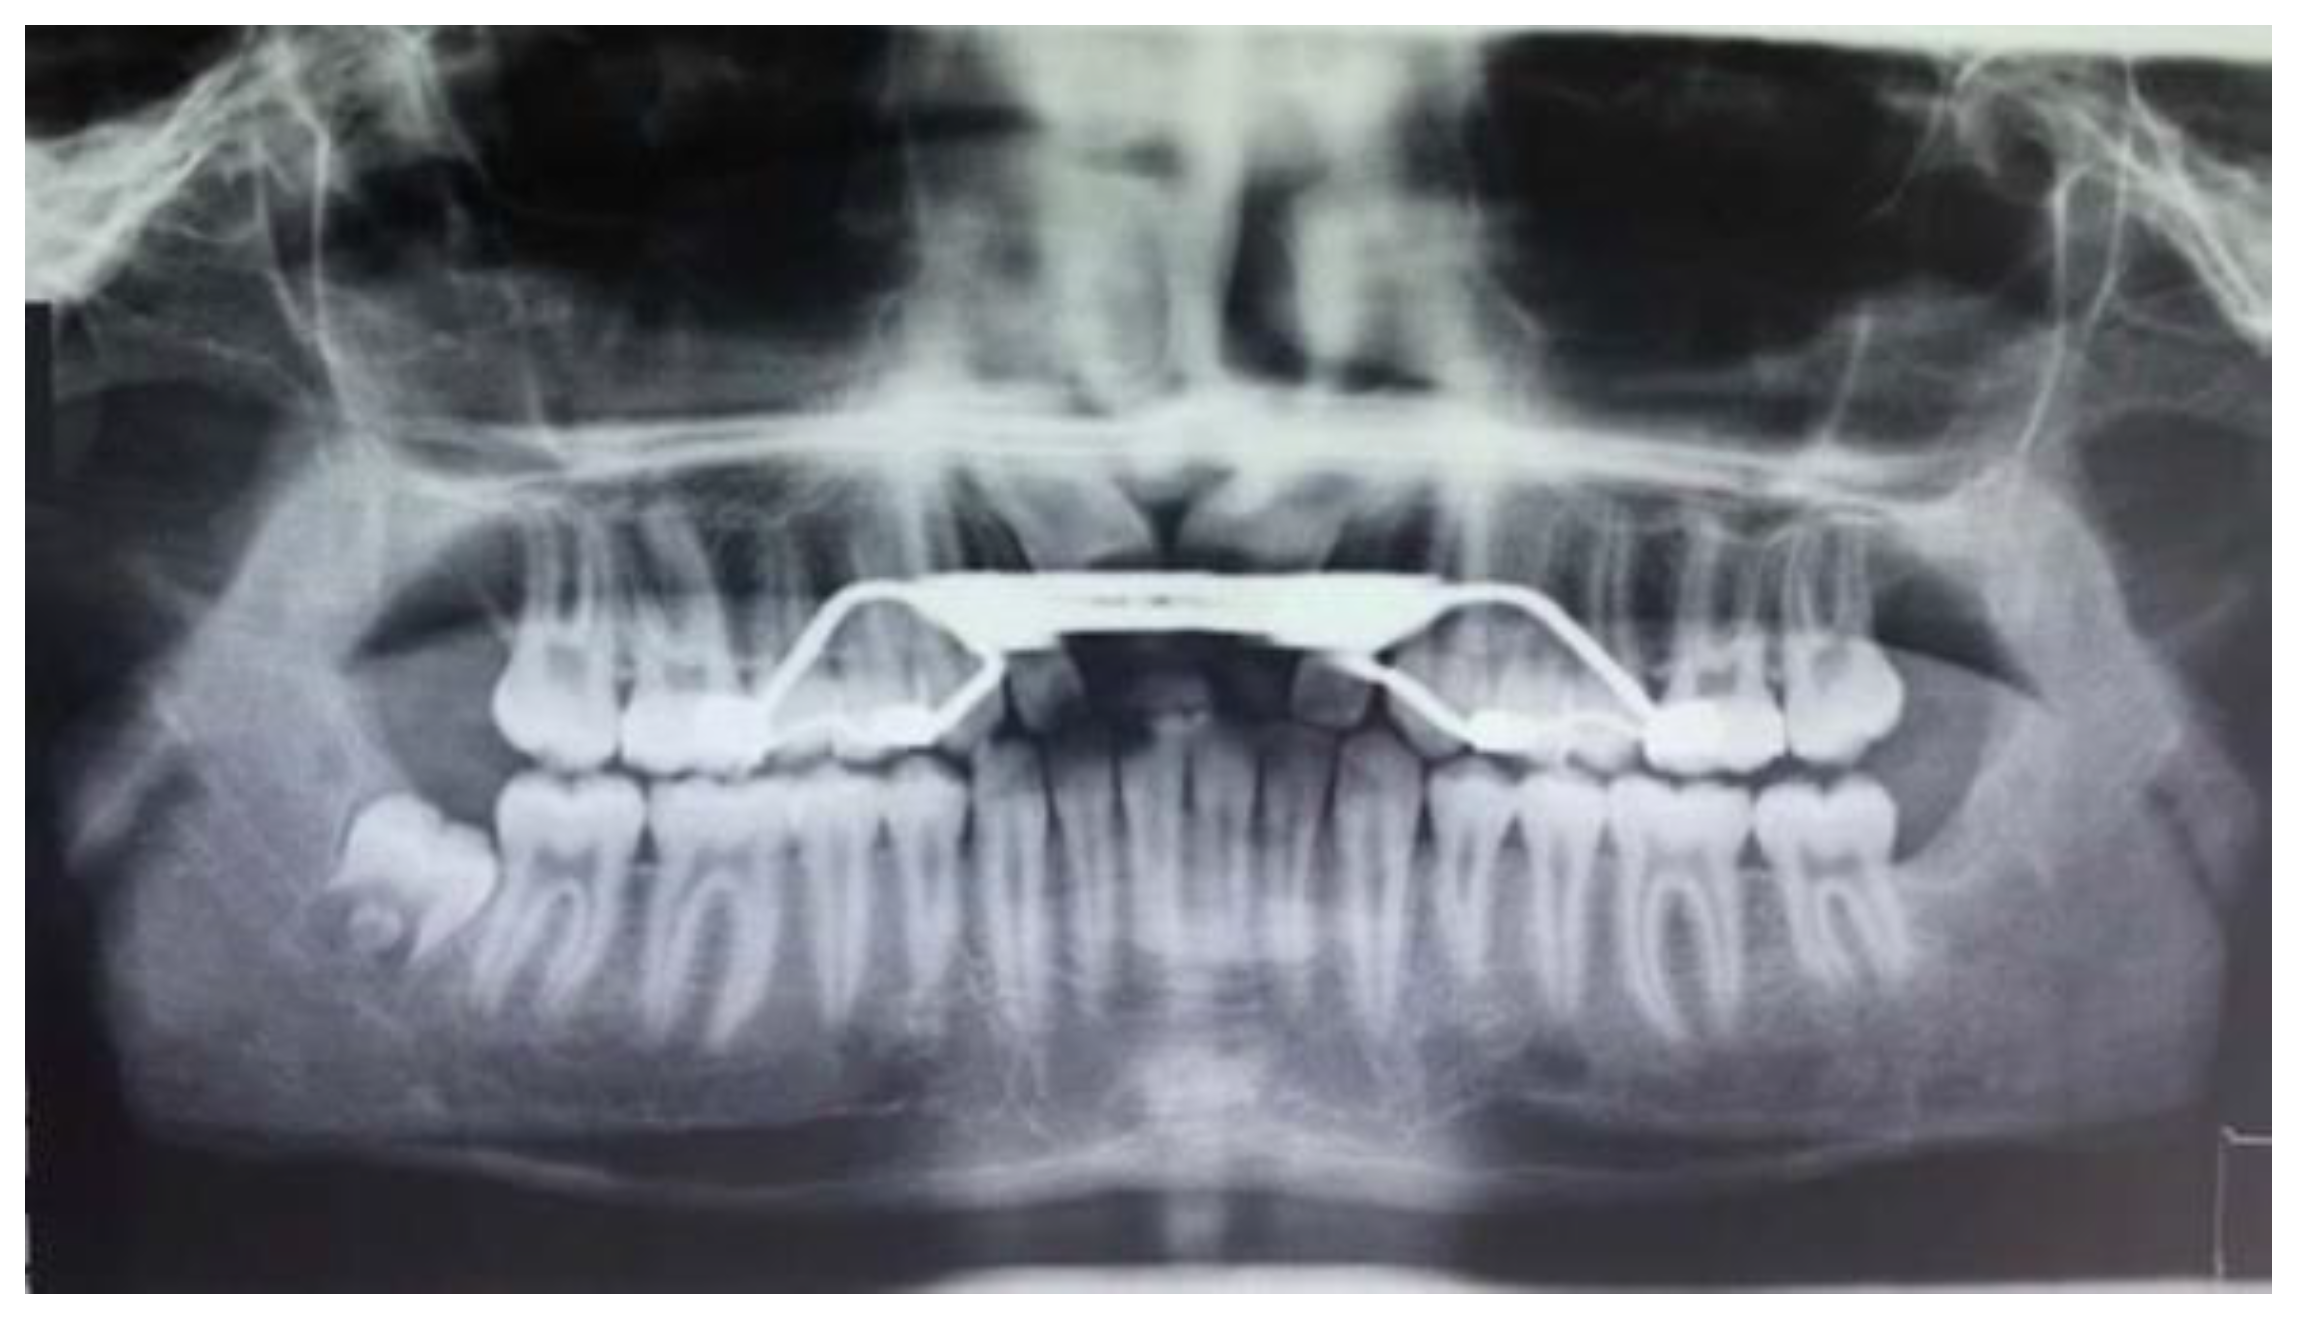

- Ortopanthomography X-ray (OPG X-ray) to evaluate the problem in relation to the entire arch, adjacent tooth and the staging of the eruption of the other dental elements.

2. Case Report

2.2. Clinical Exams and Diagnosis

3. Results